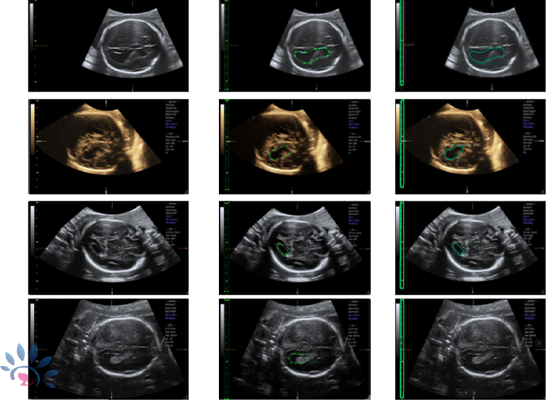

Fetal Neurosonogram

Ultrasound has been used for nearly 30 years as the main modality to help diagnose fetal CNS anomalies. Detailed evaluation of the fetal CNS (fetal neurosonogram) is also possible but requires specific expertise and sophisticated ultrasound machines. This type of examination, at times, complemented by three-dimensional ultrasound, is indicated in pregnancies at increased risk of CNS anomalies.